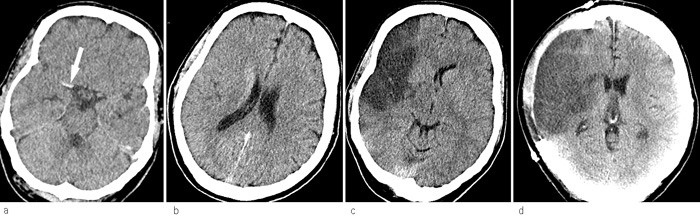

Trombemasser i a. cerebri media kan ses på CT uten kontrast hos én av fire pasienter med kliniske tegn til infarkt i a. cerebri medias forsyningsområde (fig 1a) (25). En hyperdens a. cerebri media varsler sekundær forverring med en sensitivitet på 89 % og en spesifisitet på 60 % (26). Tidligere tegn til hjerneødem ved CT ses som hypodensitet i basalgangliene og ved at grensen mellom grå og hvit substans blir vanskeligere å definere på syk side (25). Andre tidlige tegn er redusert volum av fissura Sylvii og utplanert kortikalt relieff. Etter 3 – 6 timer er det hypodensitet i infarktområdet, på figur 1a og figur 1b ser man at et økende hjerneødem komprimerer sideventrikkelen (25). Figur 1c viser hvordan midtlinjen blir forskjøvet. Ventrikkelen på motsatt side utvides når forskyvningen obstruerer tredje ventrikkel og foramina Monroi.

Hjernearterienes perfusjonsområder er ikke så konstante som det man vanligvis tror (27). Følgene av en okkludert a. cerebri media kan derfor variere. Det kan være bedre å semikvantitere tidlige funn på CT med for eksempel ASPECT-skår (The Alberta Stroke Program Early Computed Tomography score) (28). Tidlig utbredt hypodensitet er en markør for dårlig prognose og tilsier oppfølging med nye CT-undersøkelser uavhengig av kliniske symptomer. Diffusjonsvektet MR er i ferd med å bli en etablert metode, men CT har fortsatt mange fordeler, ikke minst på grunn av tilgjengelighet.